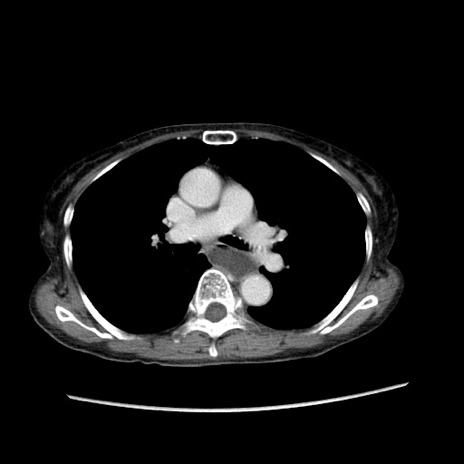

症例25(横断像)

【症例】80歳代女性

【主訴】胸のつかえ感

【現病歴】約9時間前に食後から胸のつかえた感じあり、嘔吐あり、来院。

【既往歴】胃癌(全摘)、胆摘、虫垂炎

【身体所見】心窩部に圧痛あり、反跳痛なし。

【データ】WBC 5700、CRP 0.05